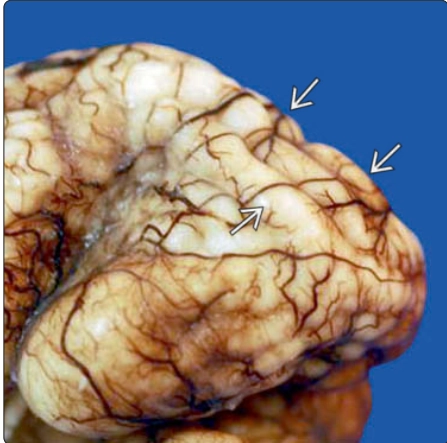

Đa hồi não nhỏ thai nhi (Polymicrogyria - PMG)